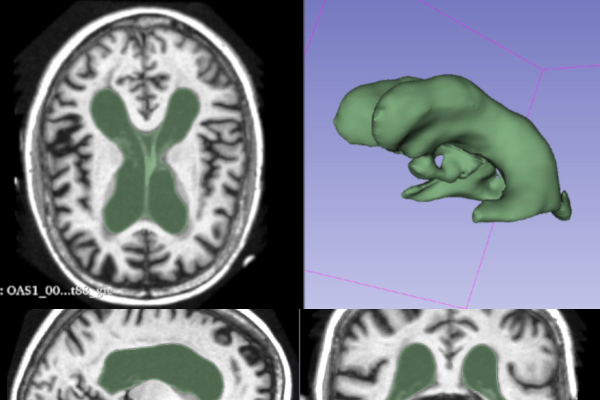

MRI Image Segmentation

Ruobing Bai, Sara Benedetti, Yakun Chen, Chun-Li Chuang, Wanchen Geng, Ruiwen Jin, Rohit Thakur, Zheying Yu

Surgery Planing From MRI

Zachary Crowell, Linhui Chen, Yantong Lyu, Hui Ma